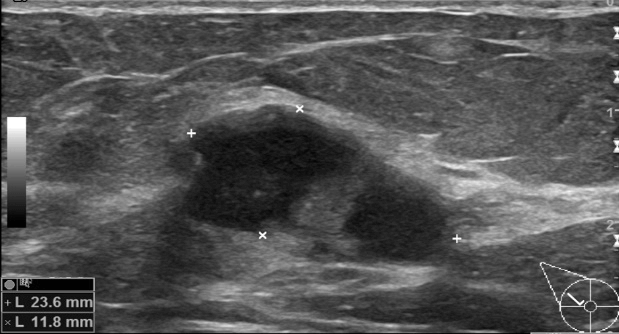

Figure 4: US examination in 2018: It showed a relatively well-defined cystic lesion with thick cystic-wall and internal septation, echogenic rim, without internal vascularity, 24x12mm in size. A complex cyst was reported and targeted for a core biopsy, causing partial collapse of the lesion. It was graded as U3 in the UK 5-point grading system (equivalent to BIRADS-4a). The sections showed cores of breast parenchyma with well-defined areas composed of a mixture of mucinous and epidermoid epithelial cells with microcyst formation (B4).

Three years later, in patient's new screening mammograms, at the area where the previously described cystic lesion was (at 10 o’ clock), a well-defined opacity was noted, larger in size compared to 2015 (Figure 3). Tomosynthesis views performed and an US scan followed (Figure 4), that showed a 24x12 mm, relatively well-defined cystic lesion without internal vascularity on power Doppler, with echogenic rim, thick cystic wall and internal septation. A complex cyst was reported and was subjected to a core biopsy, causing a partial collapse of the lesion. The radiological and clinical gradings were M3 U3 P2 (not palpable) in the 5-point UK classification system (equivalent to BIRADS-4) [10].